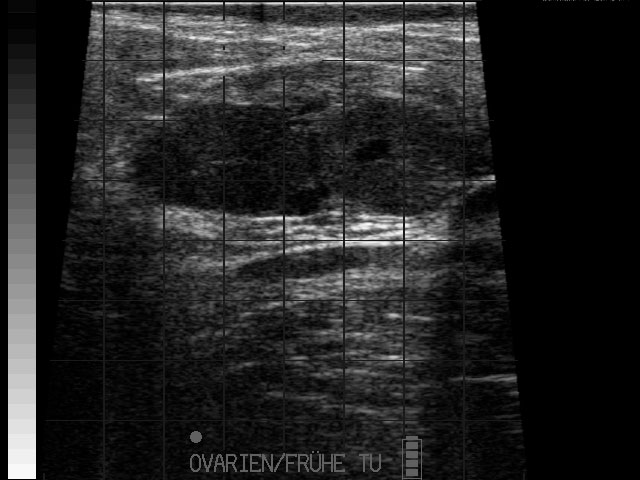

Eierstockstumor

- Erkennung von krankhaften Veränderungen der Gebärmutter, Eierstöcke oder der Harnblase